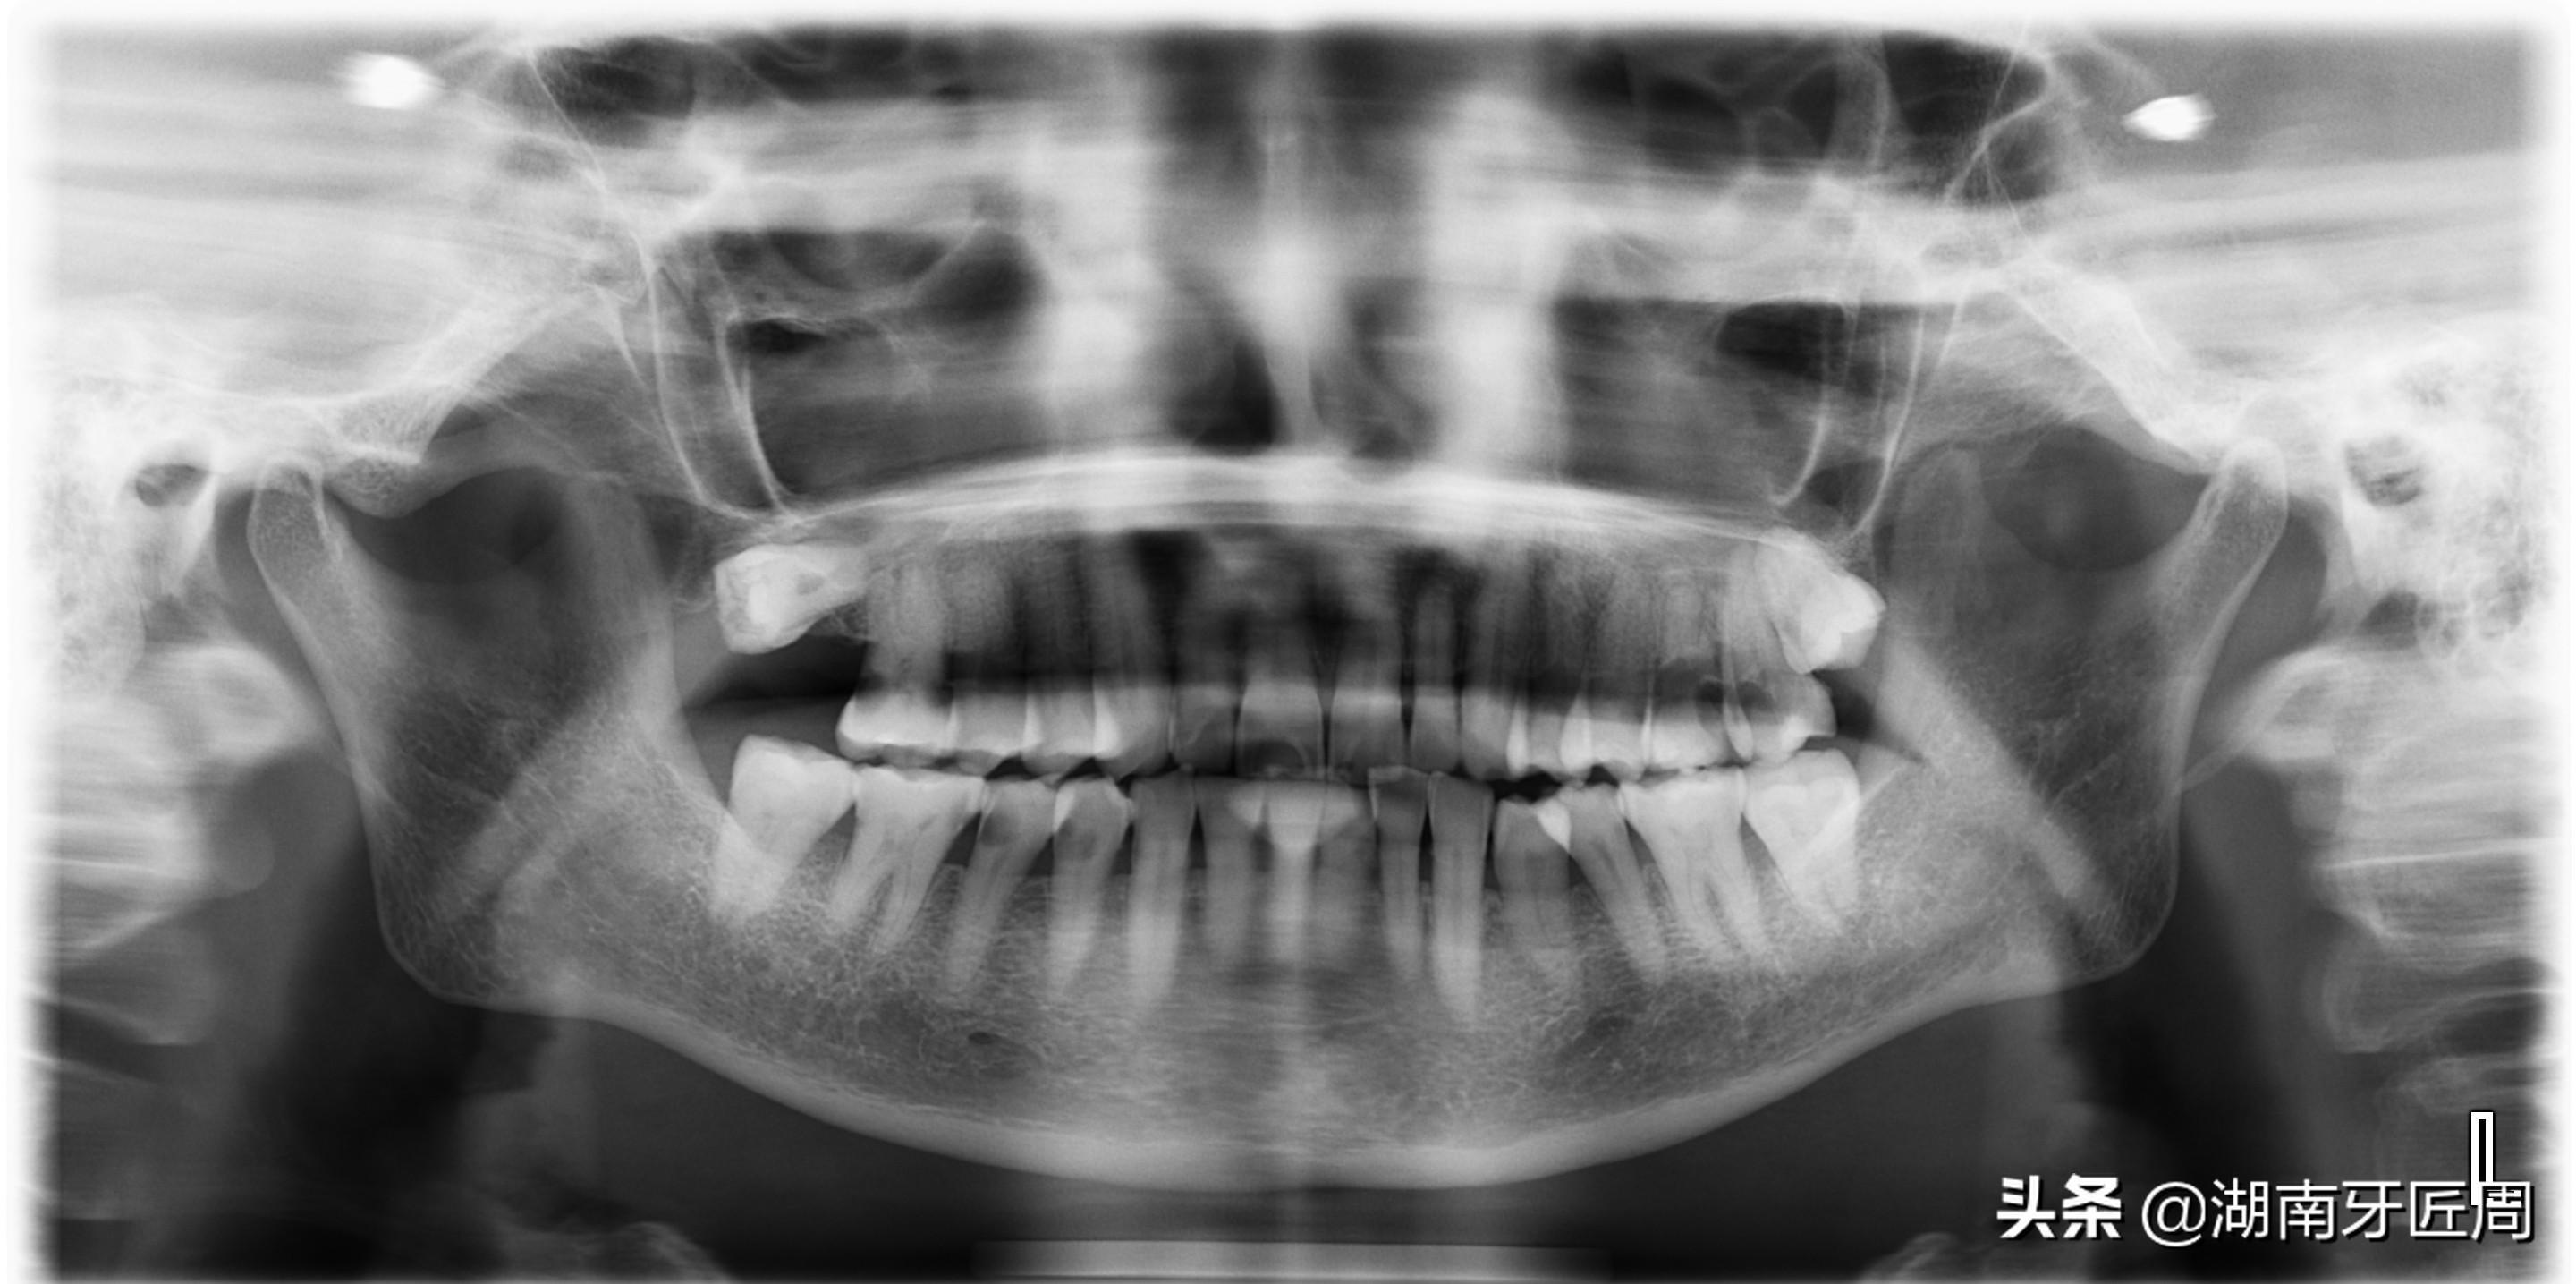

图片4.右侧智齿水平阻生,你能知道我的存在?

图片5.左侧智齿埋伏水平阻生

图片6.右侧上颌智齿接近水平阻生